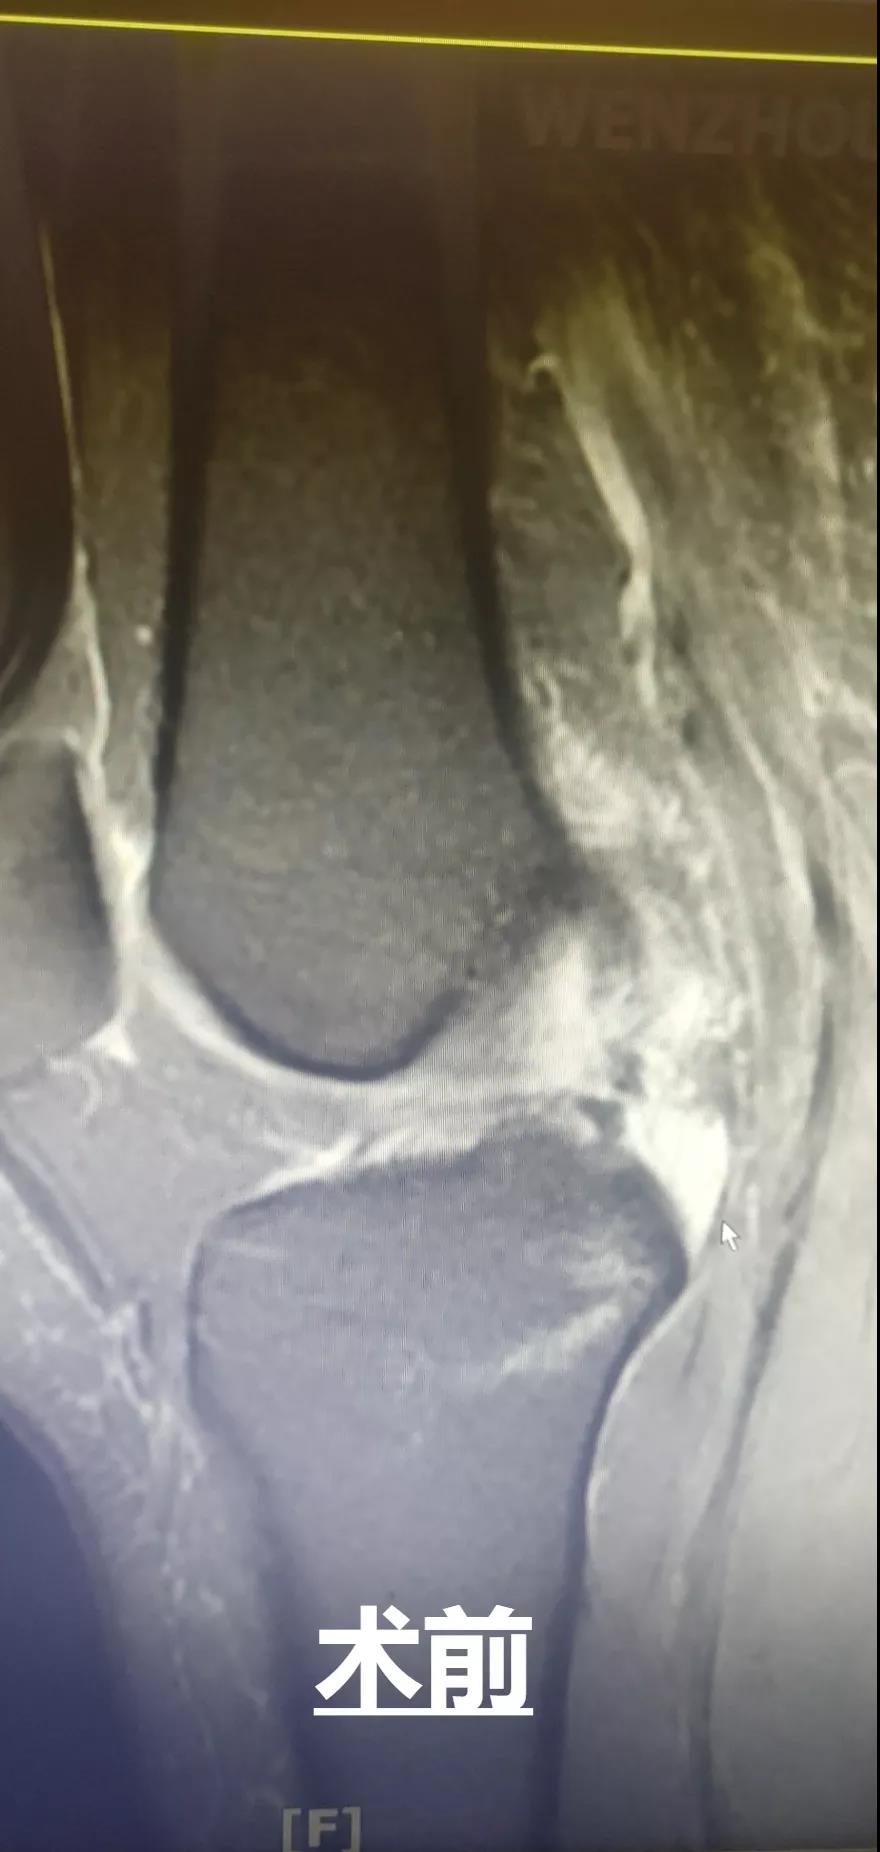

此外,和平國際醫(yī)院關(guān)節(jié)鏡微創(chuàng)團(tuán)隊(duì)還完成了一例交叉韌帶修復(fù)術(shù)。此手術(shù)采用三個約0.5cm的微小創(chuàng)口,于脛骨結(jié)節(jié)處進(jìn)行定位,后鉆通脛骨隧道,應(yīng)用多種袢鈦板進(jìn)行多位置固定,手術(shù)過程短,創(chuàng)口小,術(shù)后效果好,患者十分滿意。